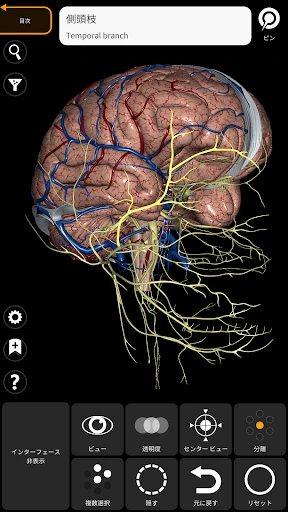

皆さん、3Dで人体を探検したことはありますか?このアプリを使うと、まるで本物の標本を手に取っているかのように、人体の構造を詳細に観察できます。何よりも嬉しいのは、非常にリアルなグラフィックスです。3Dモデルはとても精密で、筋肉や骨、内臓の位置関係が一目瞭然です。

さて、ここで気になるのは使いやすさですよね。ご安心ください!インターフェースは直感的で、スムーズに操作できます。ピンチでズームイン・アウトしたり、スワイプで回転させたりと、直感的なジェスチャーで操作可能です。このあたりは、スマホやタブレットでの操作に慣れている方なら、すぐに使いこなせるはずです。

この「解剖学 - 3Dアトラス」、ただのビジュアルツールにとどまりません。かなり多くの情報が詰まっています。例えば、各部位の詳細な説明や、医学用語の解説も充実しているので、学習にはもってこいです。特に、試験勉強中の学生さんには非常に役立つことでしょう。

私のお気に入りの機能の一つは、特定の部位を選択すると、その部位に関する詳細な情報が表示されることです。これにより、単なるビジュアルだけでなく、知識を深めることができるのです。